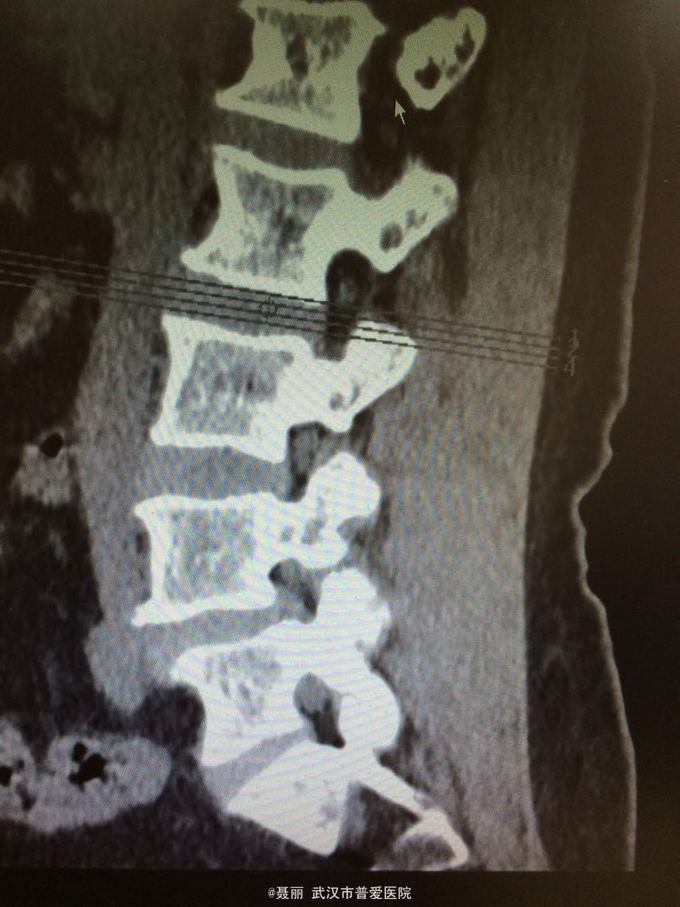

患者,女,61岁 因腰部疼痛,伴左下肢酸胀、疼痛、麻木5月余入院。 患者约5月前无明显外伤等诱因感腰腿疼痛不适,以腰部及左下肢为主,活动后左下肢疼痛加重,休息可缓解。 既往病史:既往体健,否认高血压、糖尿病等其他传染病史,否认食物药物过敏史。

辅助检查:2015年2月27号到我院拍腰椎MRI检查提示:L4椎体Ⅰ-Ⅱ度滑脱,腰椎退变。

初步诊断:腰椎滑脱症 治疗计划:1、完善相关检查:胸片、心电图,血常规,尿常规,肝肾功能电解质、术前全套 2,活血化瘀扩管治疗。卧床休息。 L4滑脱复位+L4/5椎间盘摘除、椎管减压+椎间cage3植骨融合术

:平卧位休息,加强双下肢主,被动活动,加强直腿抬高锻炼及腰背肌锻炼。2.可佩戴腰部支具逐步下地活动 ,避免弯腰负重,服用营养神经药物治疗,一个月后复查 恢复良好